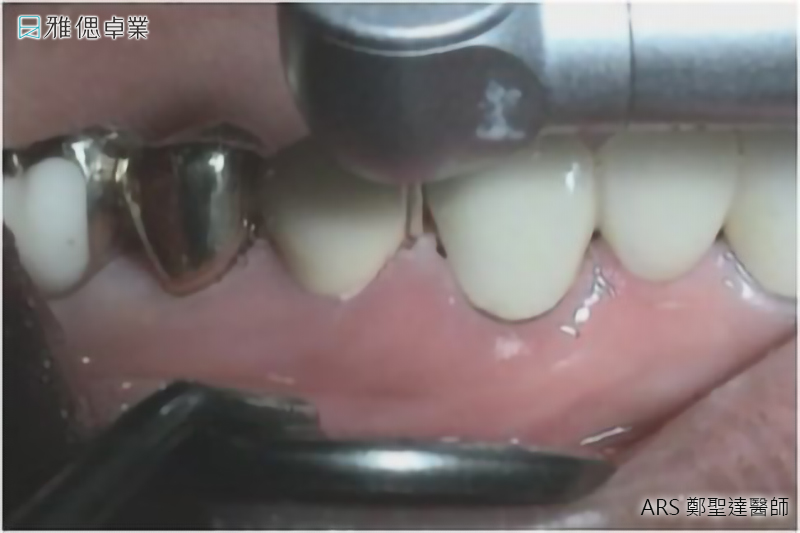

水雷射牙齦美白

- 以水結合雷射切割,切除暗沉牙齦

- 微創治療傷口更小,有效降低出血量

- 精準及細緻的切割,對牙周組織傷害較小

- 刺激牙齦組織再生進而達到牙齦美白的效果

若是配戴金屬假牙的病患,即使接受牙齦美白,仍須更換其他材質如陶瓷的假牙,才能避免黑色素再次沈澱。另外,牙周病的患者牙齦可能發炎、紅腫,必須先治療牙周病,才能接受牙齦美白。